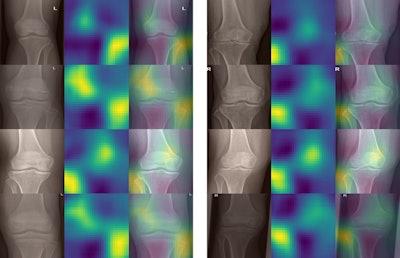

To understand how the network made its decisions from the x-rays, the researchers applied occlusion sensitivity maps for rough estimates of which parts of the knee x-ray contributed to a given decision. As expected, the fibula seemed to be the most important part for determining the anatomical side of the x-ray, the authors wrote.

Unexpectedly, in many images a second hot spot was visible on the opposite side of the fibula and above the intercondylar area. This indicates the model seemed to take into consideration the slant of the lower end of the femur, which seems also to be a rather good indication of whether the knee is a left or right one, the researchers wrote.